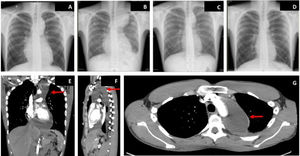

On arrival, blood pressure was 115/80mmHg, heart rate was 110 bpm, baseline oxygen saturations were 95%, and temperature was 37.2°C. On examination, a pericardial rub was noted. Electrocardiogram showed shortened PR interval and diffuse concave ST-segment elevation with normal voltages. Chest X-ray showed marked mediastinal widening (figure 1A) that prompted us to perform urgent computed tomography (CT) to rule out acute aortic syndrome: this showed bilateral pleural effusion and pericardial effusion with substantial extension into the superior aortic pericardial recess, with pericardial enhancement after administration of intravenous contrast (figure 1E-G). The aorta, pulmonary arteries, and lung parenchyma showed no significant abnormalities.

The patient was slow to improve, with persistent chest pain, temperature spikes, increased C-reactive protein up to 329 mg/dL with normal procalcitonin, radiological worsening (figure 1B) and increase in the pericardial effusion (up to 2.2 cm posterolaterally) but without hemodynamic compromise. He was therefore started on intravenous corticosteroids (0.5mg/kg/24h). In the following 48hours, the patient showed clear improvement, both clinically and on blood tests. One week later, echocardiogram no longer showed pericardial effusion, but the pericardial cyst persisted. Markers of myocardial damage were normal throughout. Blood cultures were negative.

After improving clinically, on blood tests, and radiologically (figure 1C), the patient was discharged. However, due to the persistence of the pericardial cyst, he was referred to thoracic surgery for assessment for invasive treatment. CMR performed at 1 month showed complete resolution of the pleural effusion, pericardial effusion, and associated cyst (figure 2D-F), making surgical treatment unnecessary.